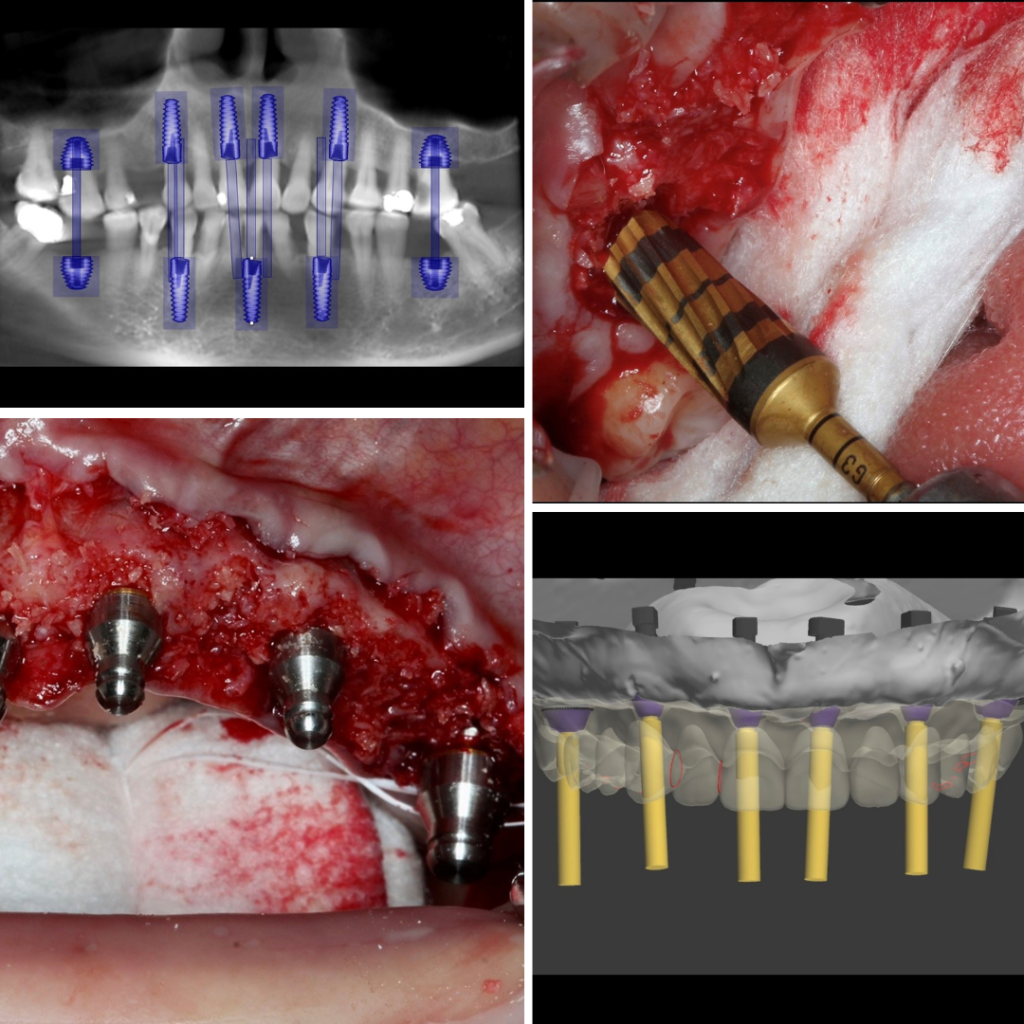

Advanced Implant Placement combined with Tuberosity Autograft & Immediate Temporization with the IDR technique.

Immediate Dentoalveolar Restoration (IDR) of compromised sockets – is a novel surgical & restorative technique invented by Dr. José Carlos Martins da Rosa